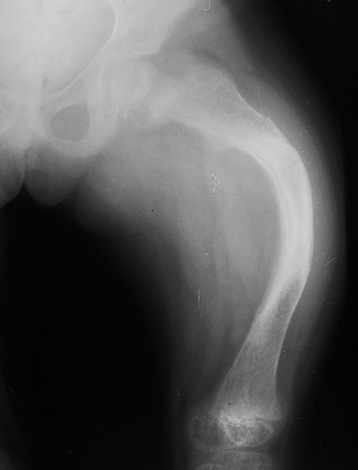

- Raquitismo - o desenvolvimento dessa condição é determinado por distúrbios metabólicos devido à falta de vitamina D. A doença se manifesta por deformações ósseas de todo o esqueleto, fragilidade e fragilidade dos ossos. Em crianças com raquitismo, existem certas alterações na forma dos ossos da mandíbula, bem como desvios sérios do desenvolvimento normal da mordida do leite.

Para esclarecer as razões, o médico pode enviar a criança para um raio-x (o estudo é realizado estritamente de acordo com as indicações, para não prejudicar o corpo da criança com radiação excessiva). Os ortodontistas, por via de regra, enviam crianças para radiografias pela primeira vez aos 4-5 anos de idade para ver como a dentição é formada e que ações podem ser tomadas agora.

Antes de tudo, o médico está interessado em saber se todos os rudimentos do leite e dos dentes permanentes estão presentes, se eles estão localizados em seus locais anatômicos, que obstáculos no caminho do dente o impedem de deixar o osso. Junto com isso, chama-se a atenção para a estrutura do seio maxilar, canal mandibular e outras estruturas importantes da região maxilofacial.